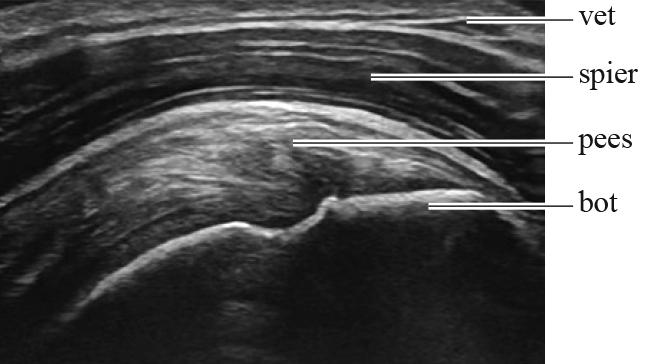

Met behulp van echografie wordt een afbeelding gemaakt van weefsel onder de huid. Zie figuur 1 en 2.